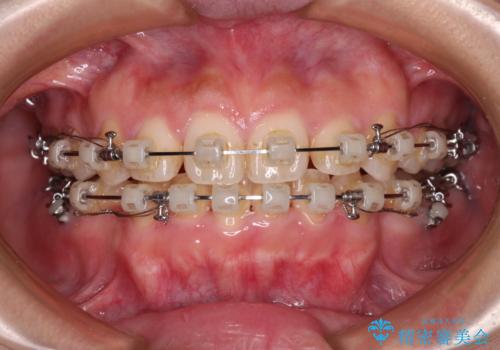

- 矯正装置

- クリアブラケット

- 治療期間

- 3年